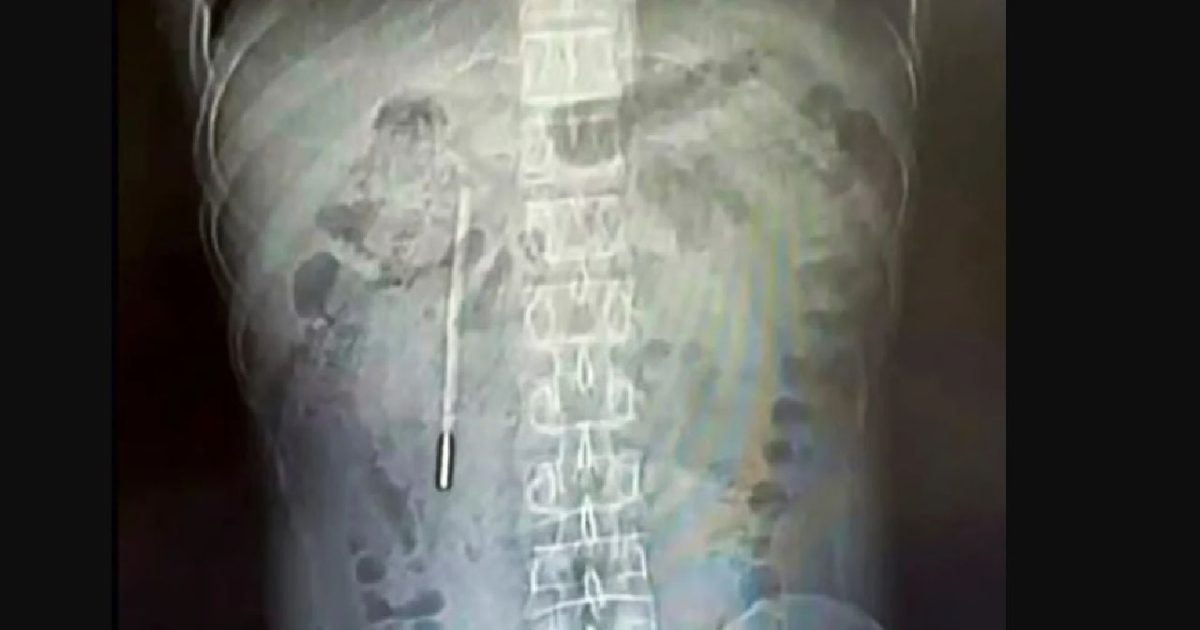

Termometru înghițit de un copil chinez, scos intact din stomac

Un termometru uitat în corp

Pacientul, identificat doar cu numele de familie Wang, în vârstă de 32 de ani, s-a prezentat la o unitate medicală din provincia Zhejiang, acuzând dureri abdominale constante. O scanare medicală a dezvăluit prezența unui obiect străin în duodenul acestuia. O radiografie a confirmat suspiciunile medicilor: era un termometru cu mercur. Vârful termometrului era poziționat riscant de aproape de peretele intestinal, crescând probabilitatea de perforație și hemoragie internă gravă.

Din fericire, medicii au intervenit prompt și au reușit să scoată termometrul intact. Deși marcajele de pe termometru se șterseseră complet, acesta a fost extras fără probleme. „A fost foarte norocos că nu a avut complicații mai grave în toți acești ani”, au declarat medicii.